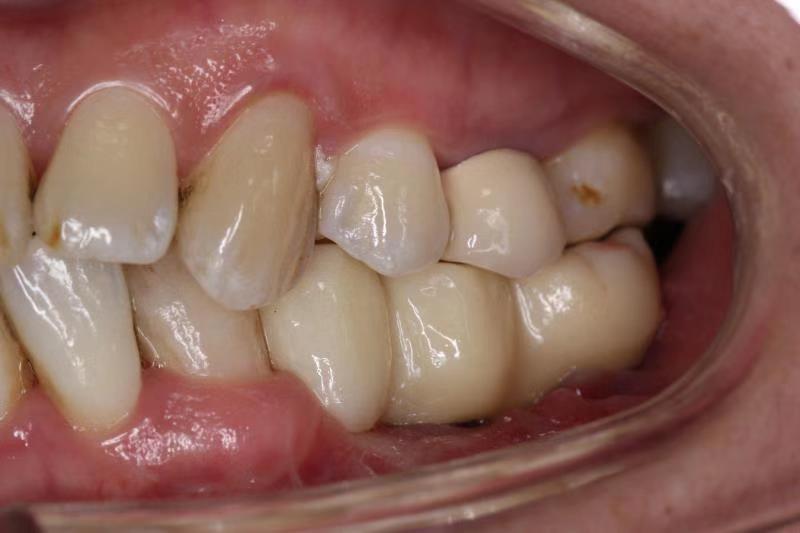

二、针对肿瘤、创伤治疗术后的复杂颌骨、牙列以及软组织缺损,采用种植技术联合骨移植进行功能性重建,尽最大程度恢复患者的咀嚼、发音以及吞咽等口腔功能,提高患者生存质量。(图为下颌骨区段缺损游离腓骨肌皮瓣移植术后行牵引成骨,二期种植行种植修复。